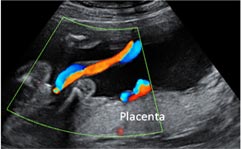

- Cordón umbilical: también se puede realizar un estudio "doppler" (exploración de la arteria umbilical) de ambos fetos, como medida complementaria del bienestar fetal.

A través de la ecografía, se valorará la cantidad de líquido amniótico de cada bolsa, medida según las denominadas columnas máximas de líquido amniótico. Al mismo tiempo, se medirán los tamaños de las vejigas de los fetos. Si en una bolsa la columna máxima de líquido amniótico es menor de 2 centímetros y en la otra es mayor de 10 centímetros, podemos decir que estamos ante un síndrome de transfusión fetofetal.